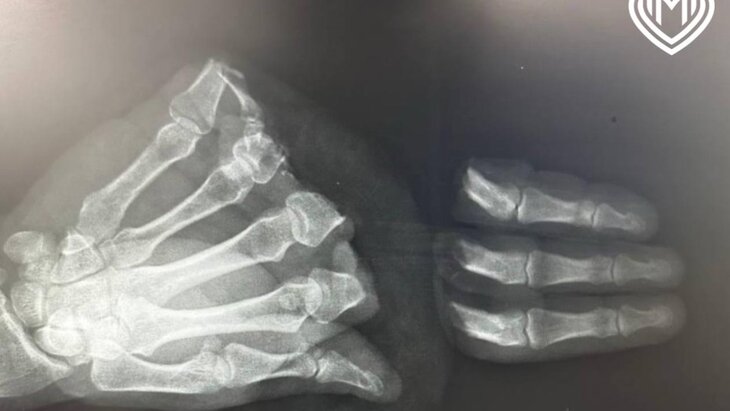

Врачи Центра микрохирургии кисти ГКБ имени Ерамишанцева оказали помощь пациенту, который случайно ампутировал себе четыре пальца правой кисти циркулярной пилой. Об этом сообщили в пресс-службе Депздрава Москвы.

Вмешательство, которое продлилось почти 13 часов, было осложнено механизмом травматического отчленения и повреждениями мягких тканей ампутированных сегментов. В результате врачи восстановили три пальца, а реплантация мизинца не представлялась возможной из-за значительных дефектов тканей.

Благодаря слаженной работе медиков пальцы полностью прижились. Спустя десять дней после операции мужчину выписали на амбулаторное лечение. В ближайшее время ему предстоит пройти длительный курс реабилитации.